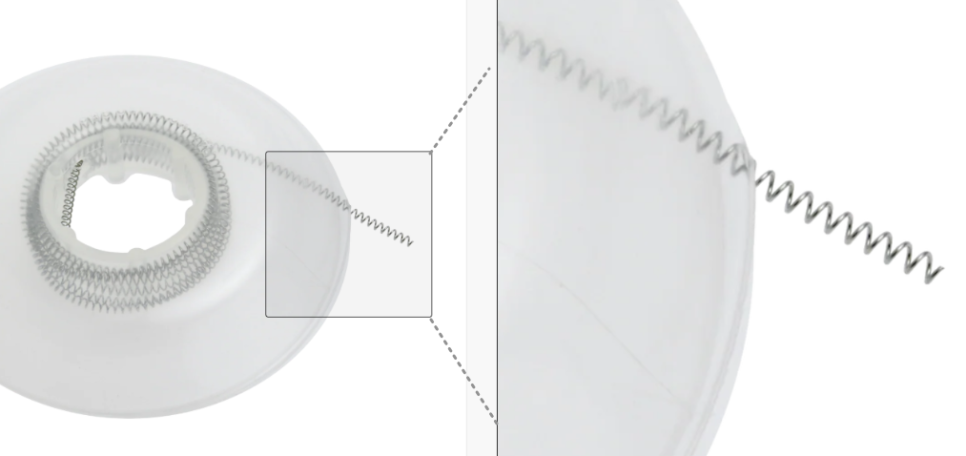

이때 필요한 장치가 바로

'오픈 코일 스프링'입니다.

오픈 코일 스프링

이름 그대로 치아 사이를

열어주는(Open) 역할을 하는

장치인데요,

원리는 의외로 간단합니다.

명일역 앞니 부분 교정

치아와 치아 사이에

압축된 스프링을 끼워 넣으면,

용수철 문을 밀었을 때

다시 튕겨 나오는 것처럼

스프링이 원래 길이로

펴지려는 힘이 발생합니다.

이 힘이 주변 치아를

옆으로 살짝 밀어내며

공간을 만들어주는 것이죠.